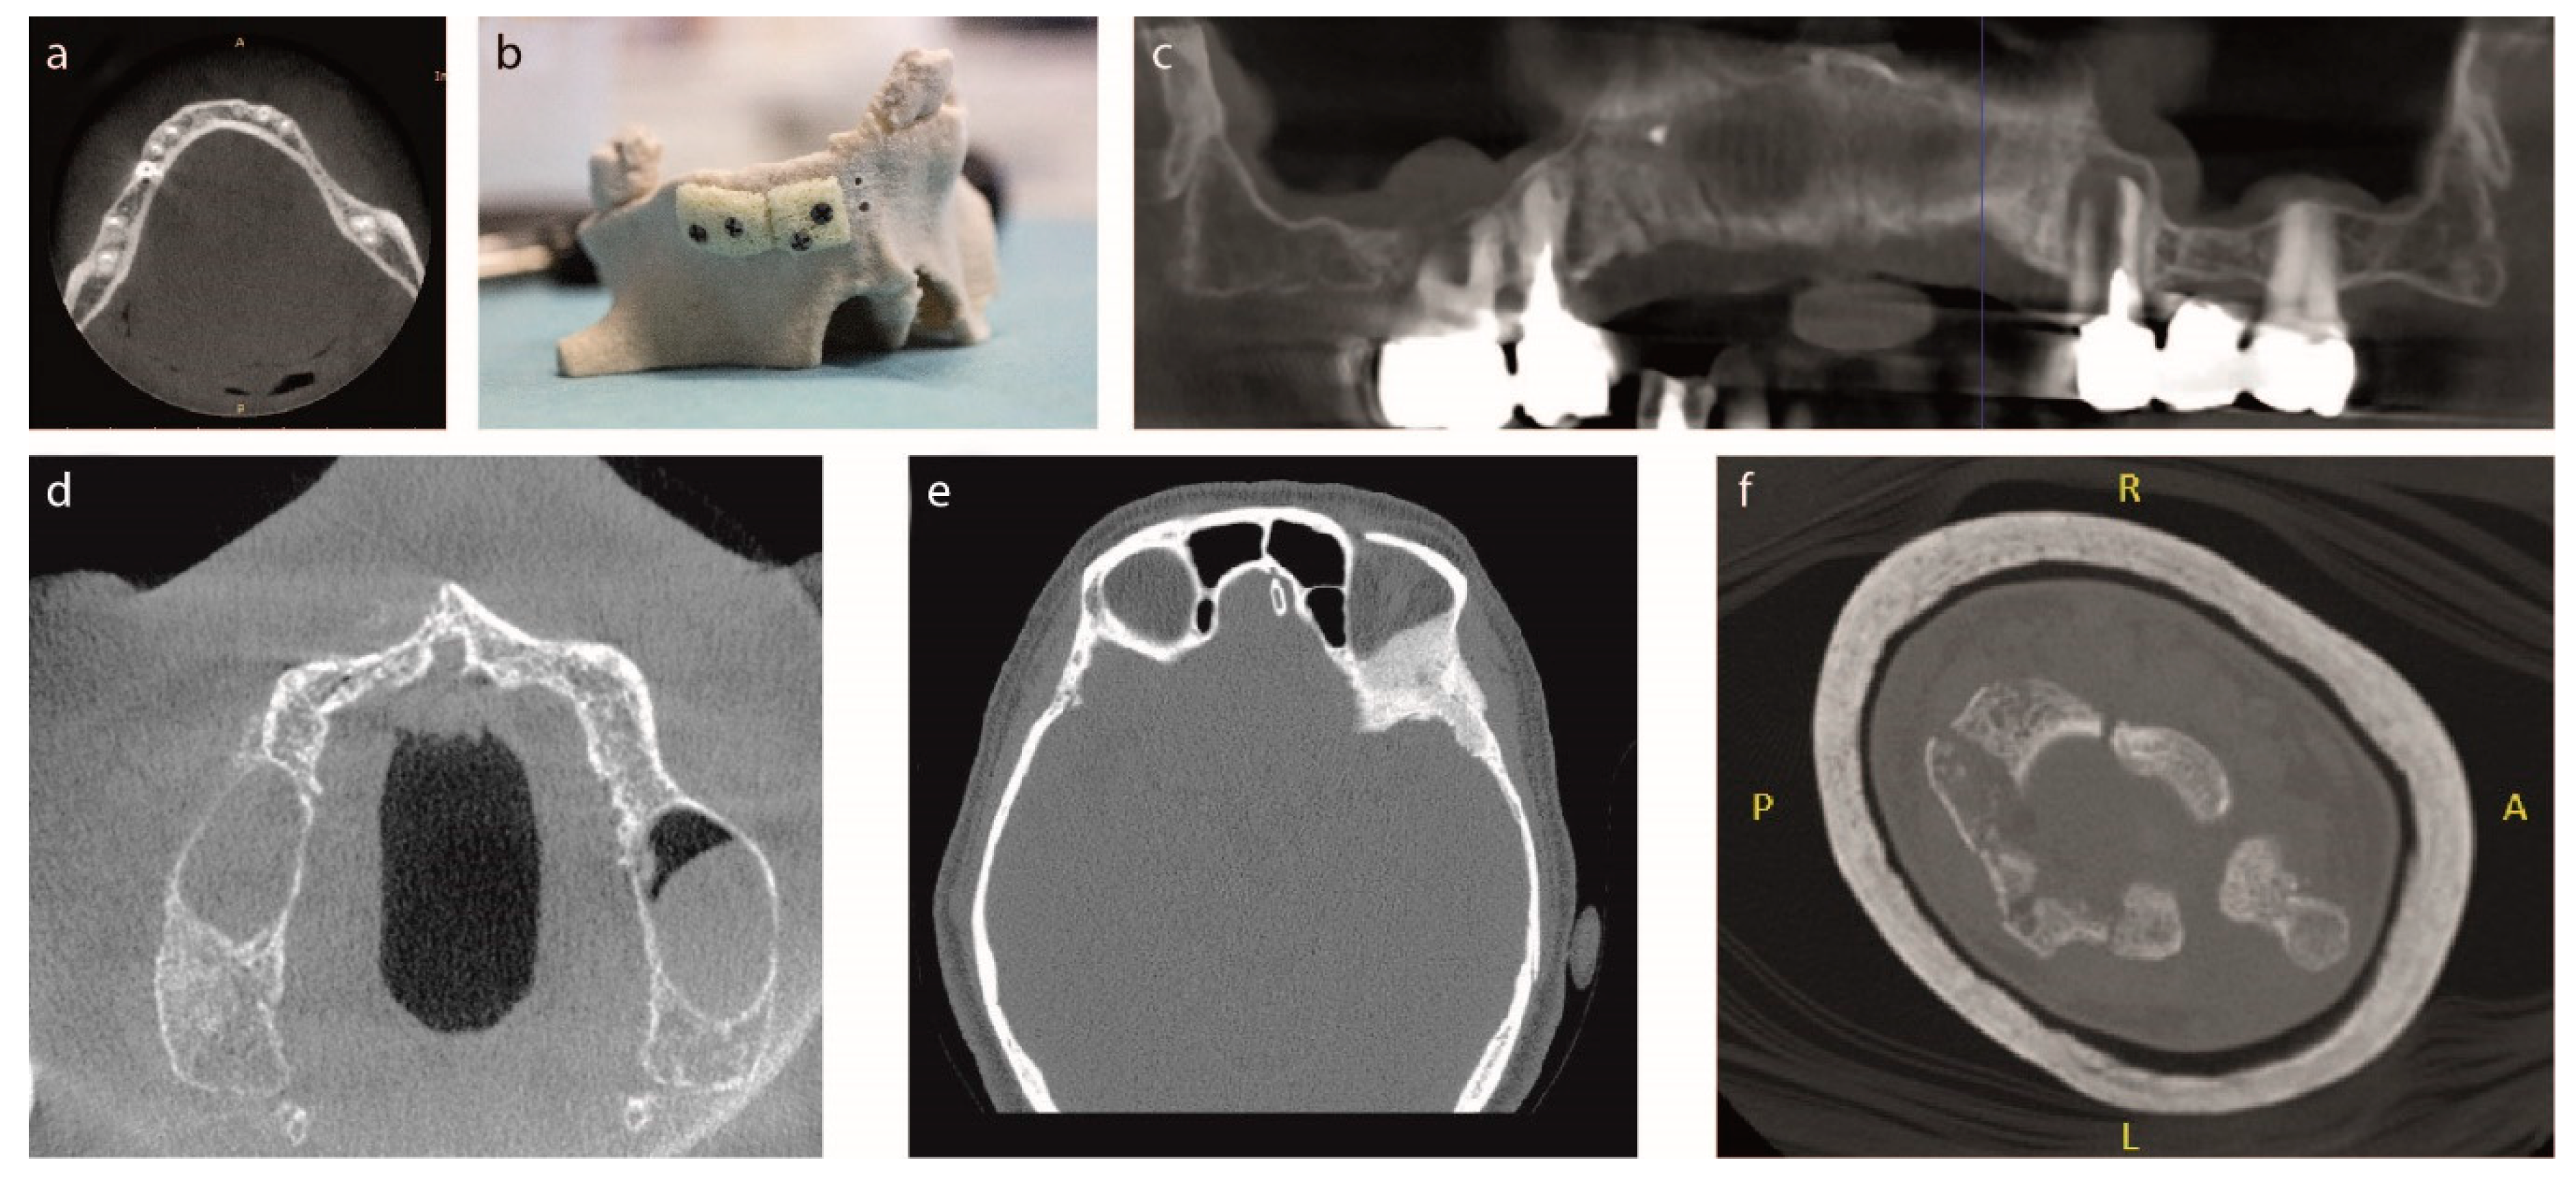

Figure 1. Initial conditions of the six investigated clinical cases. (a) Clinical case #1, patient with hypodontia in the lower dental arch; (b) Clinical case #2, sterile 3D real model of upper dental arch of partially edentulus patient, with bed-side hand cut SmartBone® blocks; (c) Clinical case #3, CBCT scan of upper arch of patient’s severe edentulia; (d) Clinical case #4, CBCT scan of upper arch of patient’s severe edentulia; (e) Clinical case #5, CT shows meningioma tumor located at the back of the right eye; (f) Clinical case #6, CT slice showing apex of the radial bone defect. - Case #2: The second patient, 57-year-old female, smoker, showed partial edentulia and lack of bone and teeth from 21 to 27 throughout the upper right dental arch, as diagnosed by CBCT. The patient’s jaw was rebuilt based on CT and surgeon cut SB standard blocks on a sterile 3D model of the patient’s anatomy (Figure 1b). A “periosteal elevation” was further performed, a procedure by which the periosteum together with the soft tissues is removed from the bone, to allow the positioning of the customized SB graft. The custom-made block grafts were implanted within the bone defect area. Screws in the bone stabilized the graft. After checking the stability of the system and having the screws firmly positioned, the incision was sutured; soft tissues covered the bone graft, and the two gum flaps were sutured.